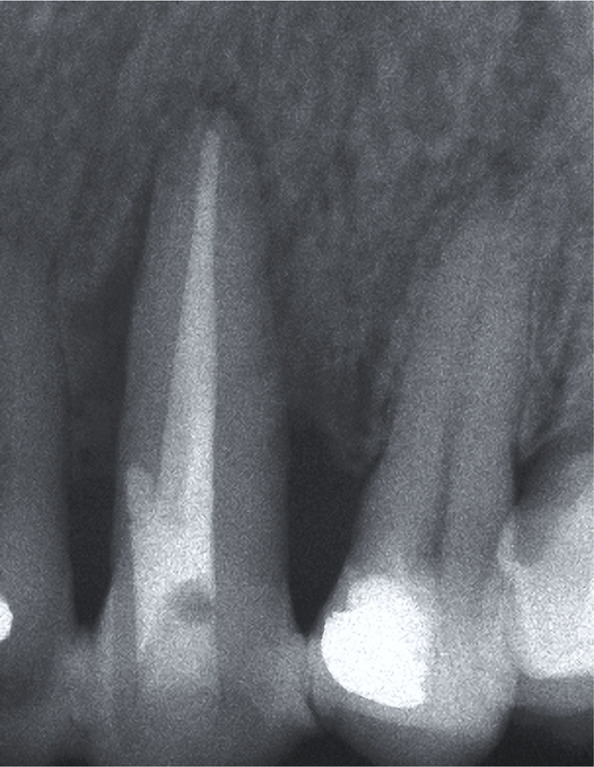

Clinical examination of tooth 23 revealed the presence of a 12 mm deep and 6 mm wide GR and keratinized tissue of 1 mm width on the buccal surface (Figure 1A). Probing depth (PD), GR and clinical attachment level (CAL) were recorded on six aspects of the tooth (Table 1). Bleeding on probing, slight supragingival calculus deposits, grade III mobility, and GR Class III, according to Miller [8], were also recorded. The initial radiographic image revealed extensive periapical and lateral radiolucency (Figure 1B).

Figure 1B:

Extensive periapical and lateral radiolucency.